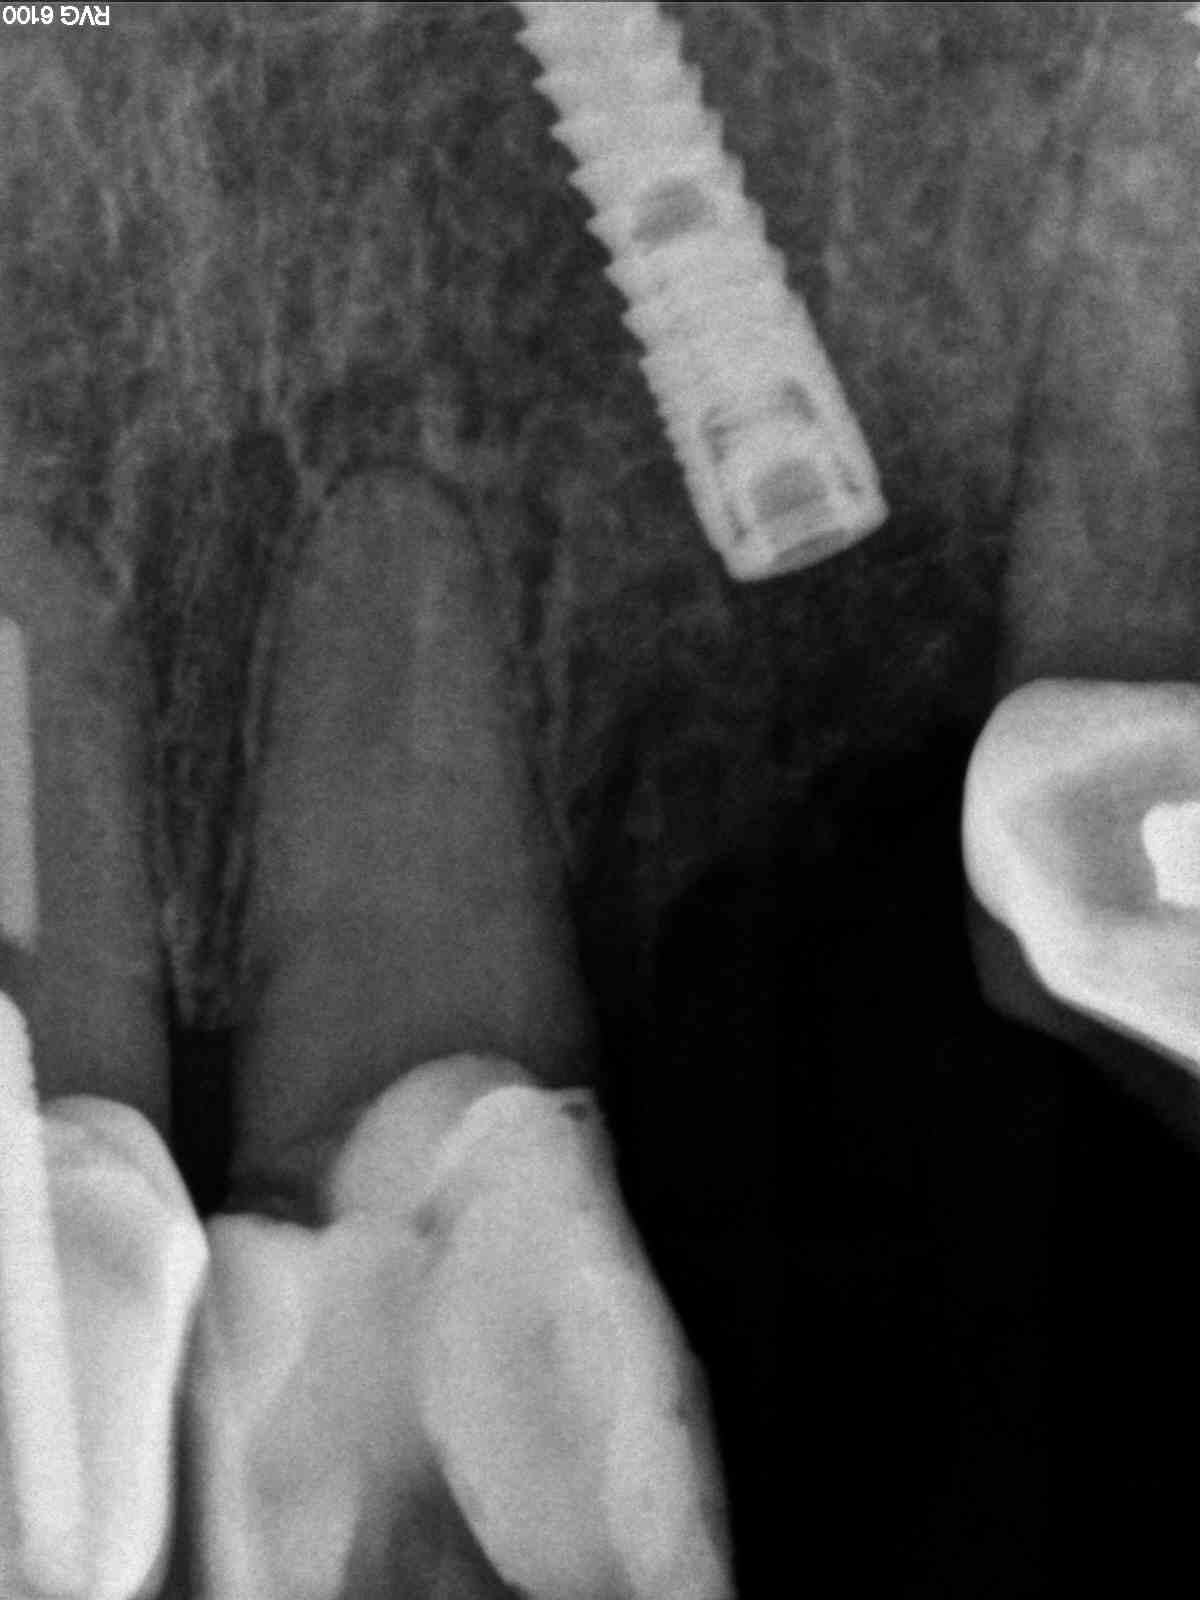

implanted r27 x ray

Knew from previous xrays that had plenty of room for length, just checking angle here

Severe angle of this makes it somewhat useless in determining position